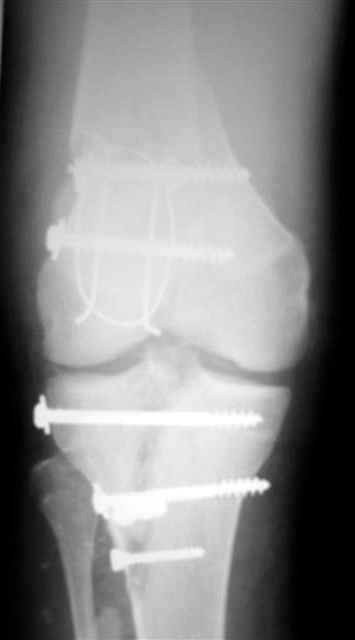

Re: открытый перелом мыщелков бедра, латерального

Alexander Chelnokov 14 Декабрь 2004, 18:23

ET> обработку и внешнюю фиксацию, картинки в приложении.

Спасибо за комментарии. Травма тяжелая с проблематичным прогнозом для функции коленного сустава( изначально травма разгибательного аппарата с последующим частичным некрозом собственной связки надколенника и о обнажением рефиксированного фрагмента бугристости большеберцовой кости, дефектом центрального отдела суставной поверхности большеберцовой кости и медиального отдела капсулы сустава).